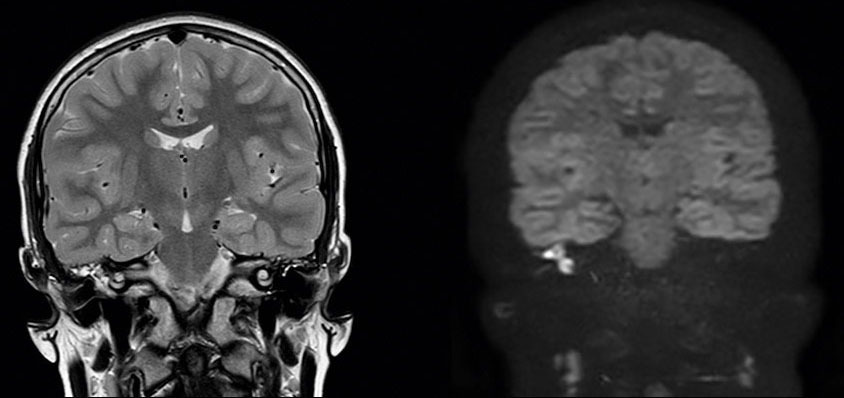

Devant ces atteintes multiples, vous demandez un scanner et une imagerie par résonance magnétique en urgence qui sont représentés ci-dessous.

Question 11 - Qu’en pensez-vous (une ou plusieurs réponses exactes) ?

Avec la séquence de diffusion à droite, qui est pathognomonique du cholestéatome.

C’est une séquence de diffusion.

L’IRM est le seul examen pathognomonique du cholestéatome. Le scanner montre la lyse osseuse mais n’est pas du tout spécifique de l’atteinte. Il n’est pas nécessaire de connaître les structures de l’oreille interne sur le scanner (qui sont très compliquées), mais il faut au moins reconnaître une oreille moyenne pleine (contenu gris) d’une oreille saine aérée (contenu en noir). On peut ensuite déduire de l’énoncé les destructions correspondantes. On aurait pu aussi dire dans cette question que le canal du nerf facial était détruit : c’est forcément le cas puisqu’il y a une atteinte du facial.